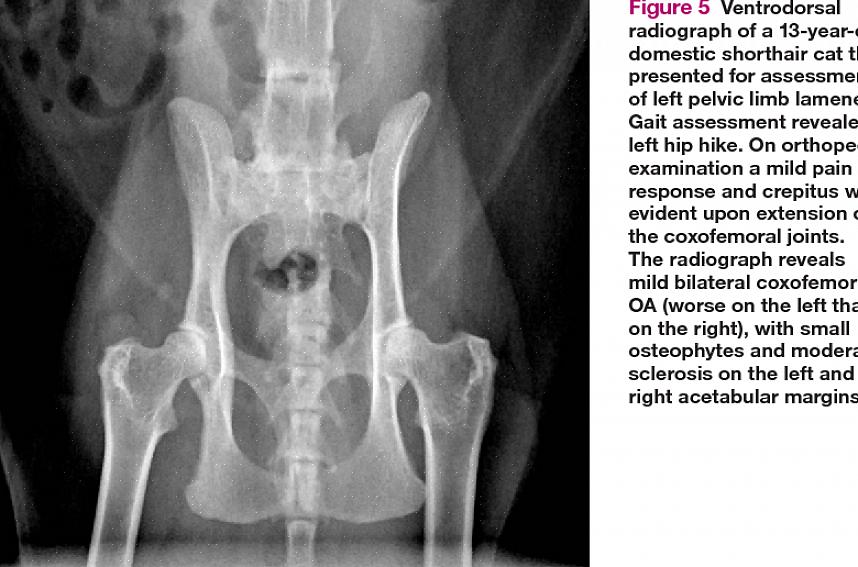

Når en katt har hoftedysplasi, utvikler lårbenshodet en uregelmessig form og sitter ikke ordentlig innenfor acetabulum. Leddet blir ustabilt, og forårsaker smerte, betennelse og stivhet. Det dårlig tilpassede leddet kan til slutt erodere brusken, slik at beinet gni sammen. I noen tilfeller blir lårbenshodet forskjøvet fra acetabulum. Over tid kan slitasjegikt oppstå og leddet utvikler unormale beinvekster. Dette begrenser bevegelsesområdet ytterligere og fører til at smerte og stivhet blir enda verre.

Din veterinær vil diagnostisere kattens hoftedysplasi grundig undersøkelse og røntgenbilder. Behandlingshensyn er basert på alvorlighetsgraden av røntgenbildene samt symptomene katten din viser.